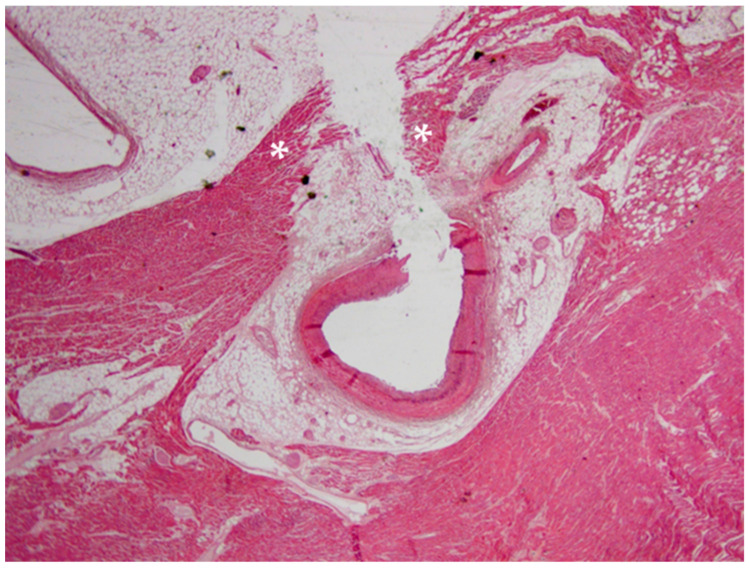

A 20-year-old young man (body mass index: 28) suddenly died in a public place. The friend who witnessed his death declared that he had recently smoked cannabis. All the witnesses said that the young man appeared in good health and that he suddenly collapsed (without any previous symptom). Basic life support maneuvers were promptly started, but when paramedics arrived, he was asystolic at ECG. The public prosecutor requested an autopsy to find the cause of the death. The victim played several competitive sports and had a syncope while playing football three years before. At external examination of the body no relevant sign was found. At the autopsy, performed five days after the death, the heart was isolated and fixated in toto in a 10% buffered formalin-based solution (Figure 1 and Figure 2). Both the lungs appeared swollen (weights: left—450 g, right—940 g), and multiorgan congestion was observed. Heart examination (weight: 530 g, longitudinal diameter: 11 cm, transverse diameter: 13 cm) presented no anomaly. Atria, valves, left ventricle (anterior wall thickness: 1.3 cm; lateral wall thickness: 1.4 cm; posterior wall thickness: 1.7 cm; interventricular septum thickness: 1.5 cm) and right ventricle (wall thickness: 0.5 cm) did not show any macroscopic relevant finding. Coronary circulation was right dominant. Left anterior descending coronary artery presented, at 2 cm from its beginning, a 0.3-cm-thick 5.5-cm-long myocardial bridging (Figure 3). Other coronary arteries were macroscopically normal. The conduction system was carefully analyzed, and serial sectioning targeted blocks of areas of interest [ref. 12,ref. 13]. Histopathological examination of the myocardium (Figure 4) found wavering of myocardial fibers, fibrosis and disarray in the left ventricle myocardial area above the MB (Figure 5); fibrosis in sino-atrial node area (Figure 6) and infiltration of fatty tissue (separated the myocardium) in the antero-lateral region of right ventricle free wall (Figure 7). The atrio-ventricular node presented no microscopic anomalies. No signs of myocarditis were found.

At the autopsy, the only relevant macroscopic finding was the myocardial bridging of left anterior descending coronary artery in the context of a normal heart. In general terms, MB is a congenital coronary anomaly (mean length: 14.64 ± 9.03 mm, mean thickness: 1.23 ± 1.32 mm) that usually affects (as in our case) the middle tract of left anterior descending coronary artery and is often found for the first time only at autopsy [ref. 30,ref. 31,ref. 32]. According to many authors, when it is particularly thick (2 mm is generally indicated as cut-off), it may cause myocardial ischemia, but it is controversial if it can be considered a possible cause of SCD [ref. 32,ref. 33]. Myocardial bridging has been also reported in men with no family history of sudden cardiac death in which the first clinical manifestations of BrS were acute chest pain and syncope [ref. 34,ref. 35]. A causal relationship between this coronary anomaly and BrS has never been proved, but Riezebos et al. hypothesized that “interaction between the provoked ischemia and the specific repolarization abnormalities that are caused by the Brugada syndrome could provide an electrophysiological substrate that may increase individual susceptibility to life-threatening ventricular tachyarrhythmias” [ref. 35].